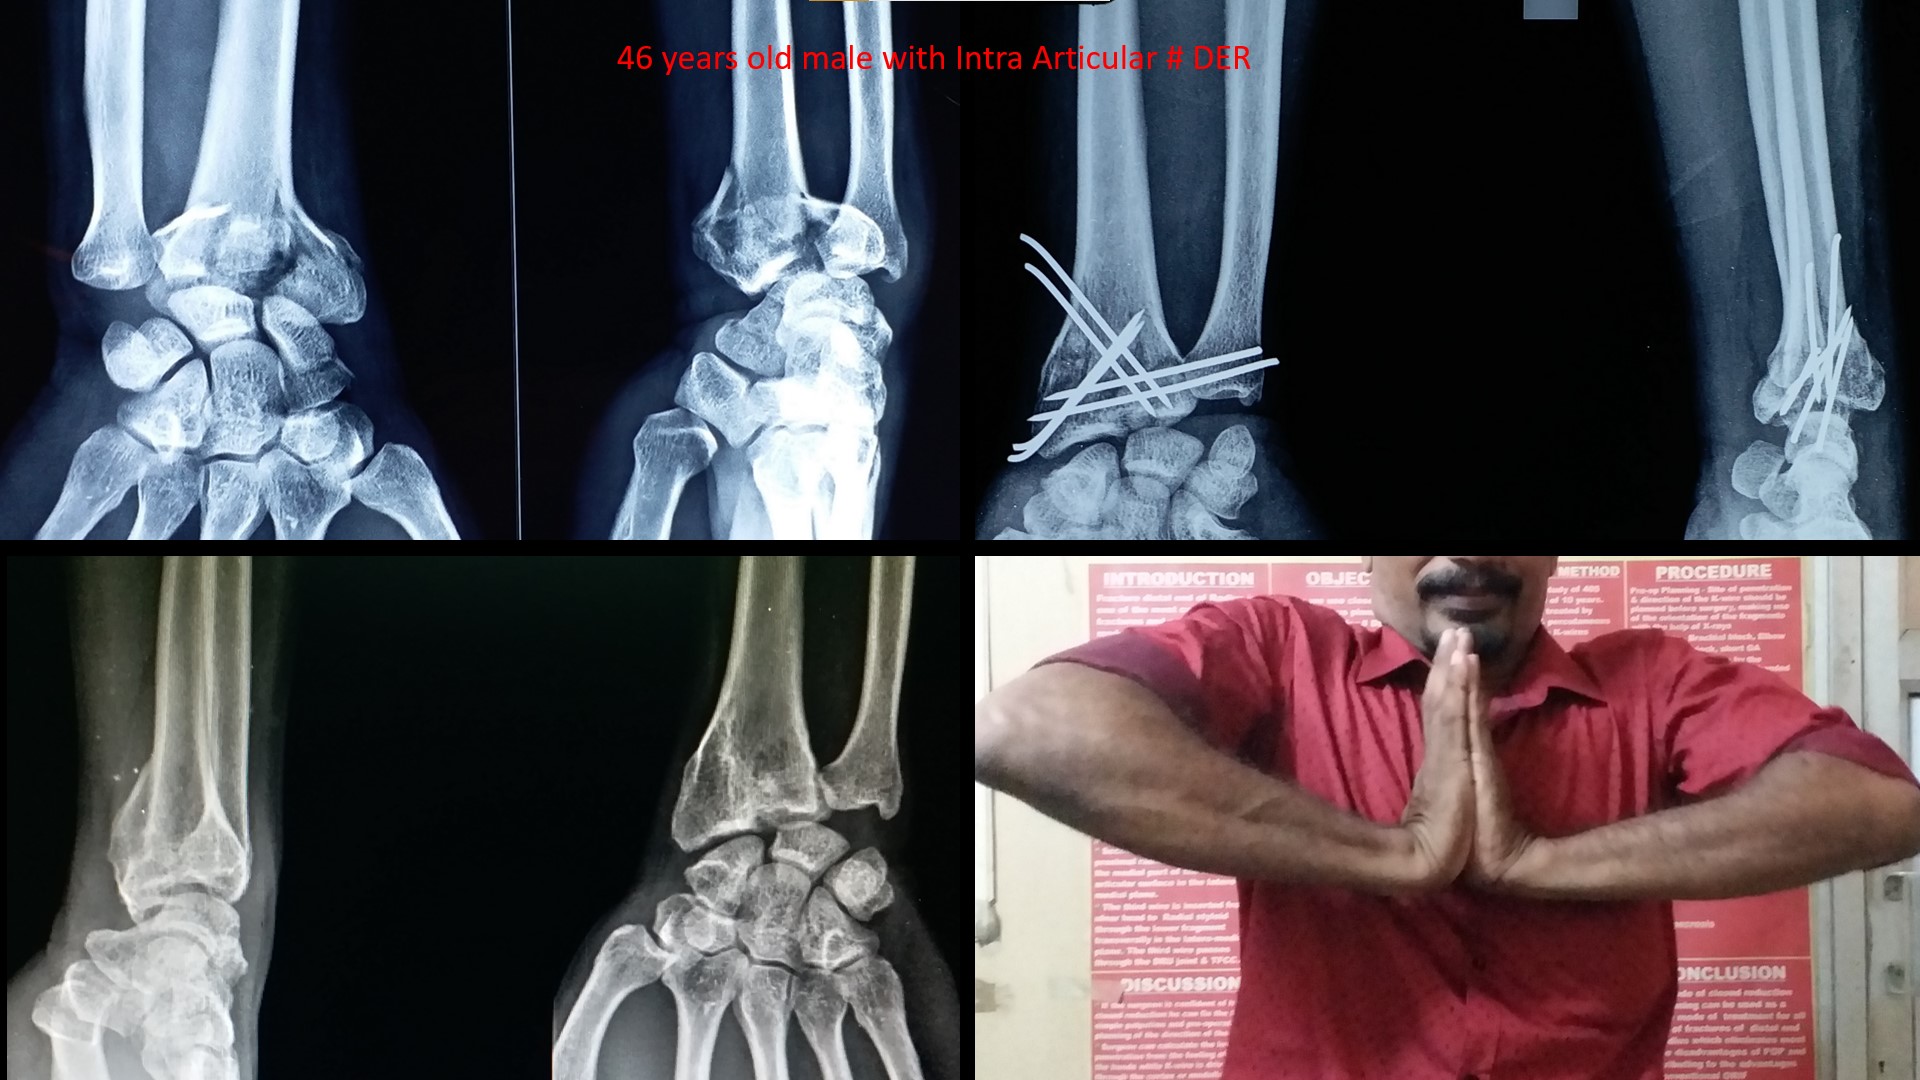

wrist